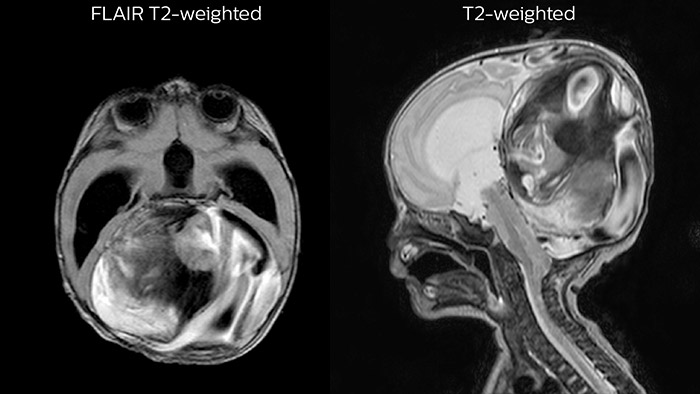

Since scan times of 3D scans can be significantly shortened thanks to Compressed SENSE, the MRI team is performing more 3D scans than before. “The advantage of 3D scanning is that we capture one high resolution sequence, but we can reconstruct images in any orientation, even after the scan, when looking at the images for diagnosis. Having this ability to view any crosssection we need in high resolution, can make re-scanning unnecessary,” says Dr Junge. “We are currently optimizing our routine head examination to include more 3D scans, including T1- weighted, T2-weighted and FLAIR.”

Leukodystrophy in a teenager

Rostral meningitis and arachnoiditis Both images are from the same 3D T1-weighted post contrast sequence in a newborn, under treatment.